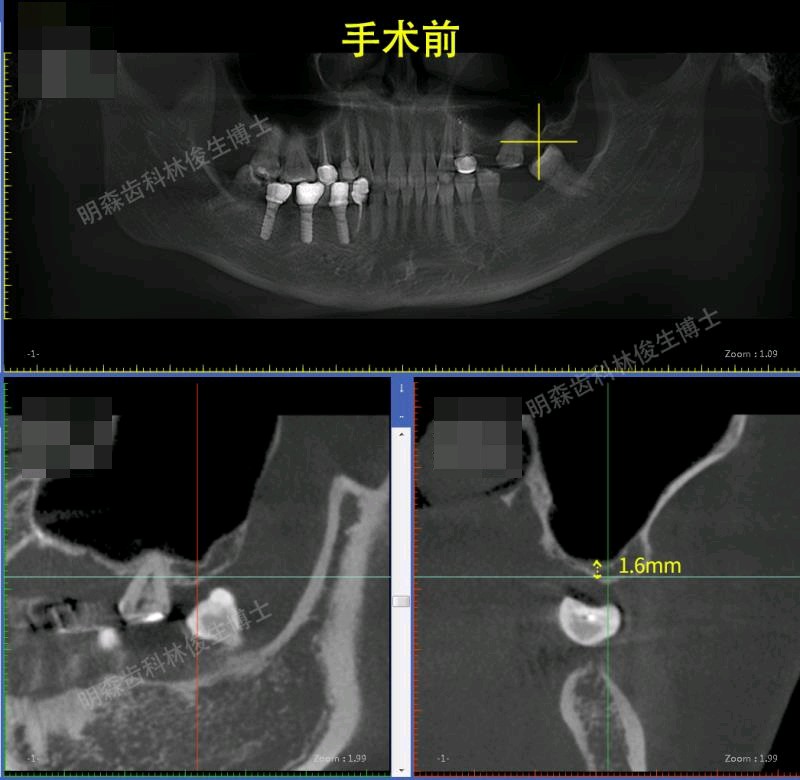

辅助检查:cbct示:25,27牙槽骨高度不足,36,37牙槽骨高度尚足

治疗方案:1.建议13-23贴面+14,15,33-43贴面修复,上前牙邻面龋补牙。 2.38.48拔除 3.24-26连冠修复,14.15换全瓷冠 4.25,27外提+植骨+种植,36,37种植修复(ITI钛锆)5.17充填治疗